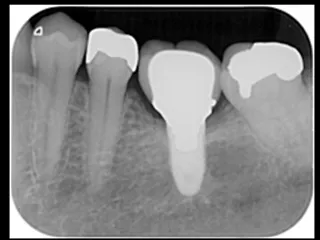

CASE No.2 奈良 嘉峰 先生(神奈川県茅ヶ崎市開業)

Labrida 施 術 前

施 術 前 (レントゲン写真)

Labrida  施 術 後(4週後 )

炎症とBOP消失

施 術 後 (レントゲン写真)